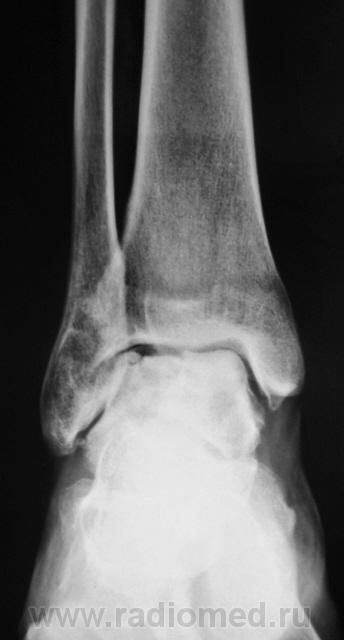

Пациент направлен на рентгенографию голеностопного сустава с диагнозом ДОА.

После внутрисуставного перелома вероятность доа оччень высока. Колгда была травма?

Травма была два года тому.

Похоже  на  остеохондропатию  блока  таранной  кости  +   ДОА.

А присутствует линейный (или лентовидный, я их путаю) остеопороз, а это признак острого процесса.

+ за лентовидный остеопроз...

Будем думать, что некроз блока таранной кости не такой уж и асептический, какая-то инхвекция там есть.

Посттравматический артроз с кистовидной перестройкойлатерального мыщелка Субхондральное уплотнение исужение суст. щелей естьИ неконгруэнтность большеберцового эпифиза к таранной маленько просматривается?